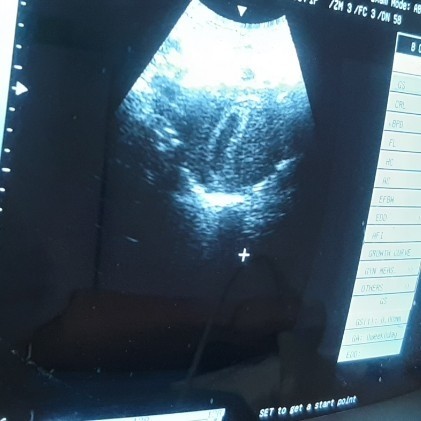

8w4d USG belum kelihatan janin

hi moms aku mau nanya tadi aku usg tapi janin belum kelihatan hanya kantungnya saja. tadi lupa minum air juga sebelum usg apakah itu berpengaruh sehingga janin tidak kelihatan? mohon info mom takutnya ini BO ?